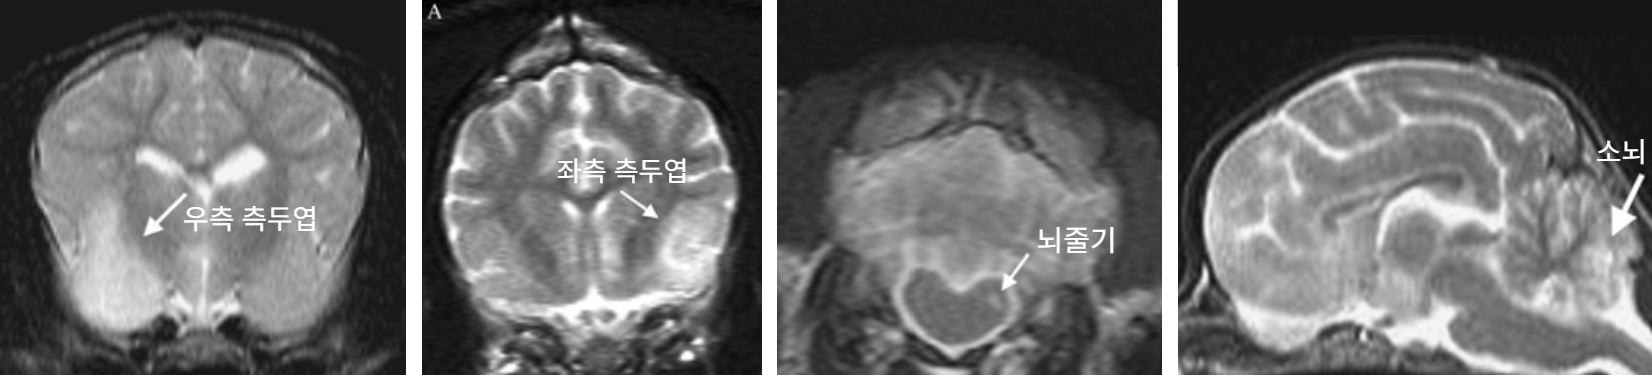

| ์์์ ์ถ๋ก | โ Young โ History : Mild to severeํ ์์ฅ๊ด ๋ฐ ํธํก๊ธฐ ์ฆ์์ด ์ ๊ฒฝ๊ณ ์ฆ์์ผ๋ก ์งํ๋จ โ ํ์ก ๊ฒ์ฌ : lymphopenia, mild thrombocytopenia (๋ฆผํ๊ตฌ, ํ์ํ ๊ฐ์) โ ๋ฐฉ์ฌ์ ๊ฒ์ฌ : interstitial & alveolar infiltrates (๊ธฐ๊ด์งํ๋ ด) โ MRI : T2-Weighted image์์ ๊ตญ์ํ๋ hyperintense ๋ณ๋ณ๋ค ๊ด์ฐฐ (์๋, ๋์ค๊ธฐ, ์๋, ์ฒ์ ๋ฑ) ใ* MRI์ ๋ณ๋ณ ์๋ ๊ฒฝ์ฐ๋ ์์ ใ ![]() |